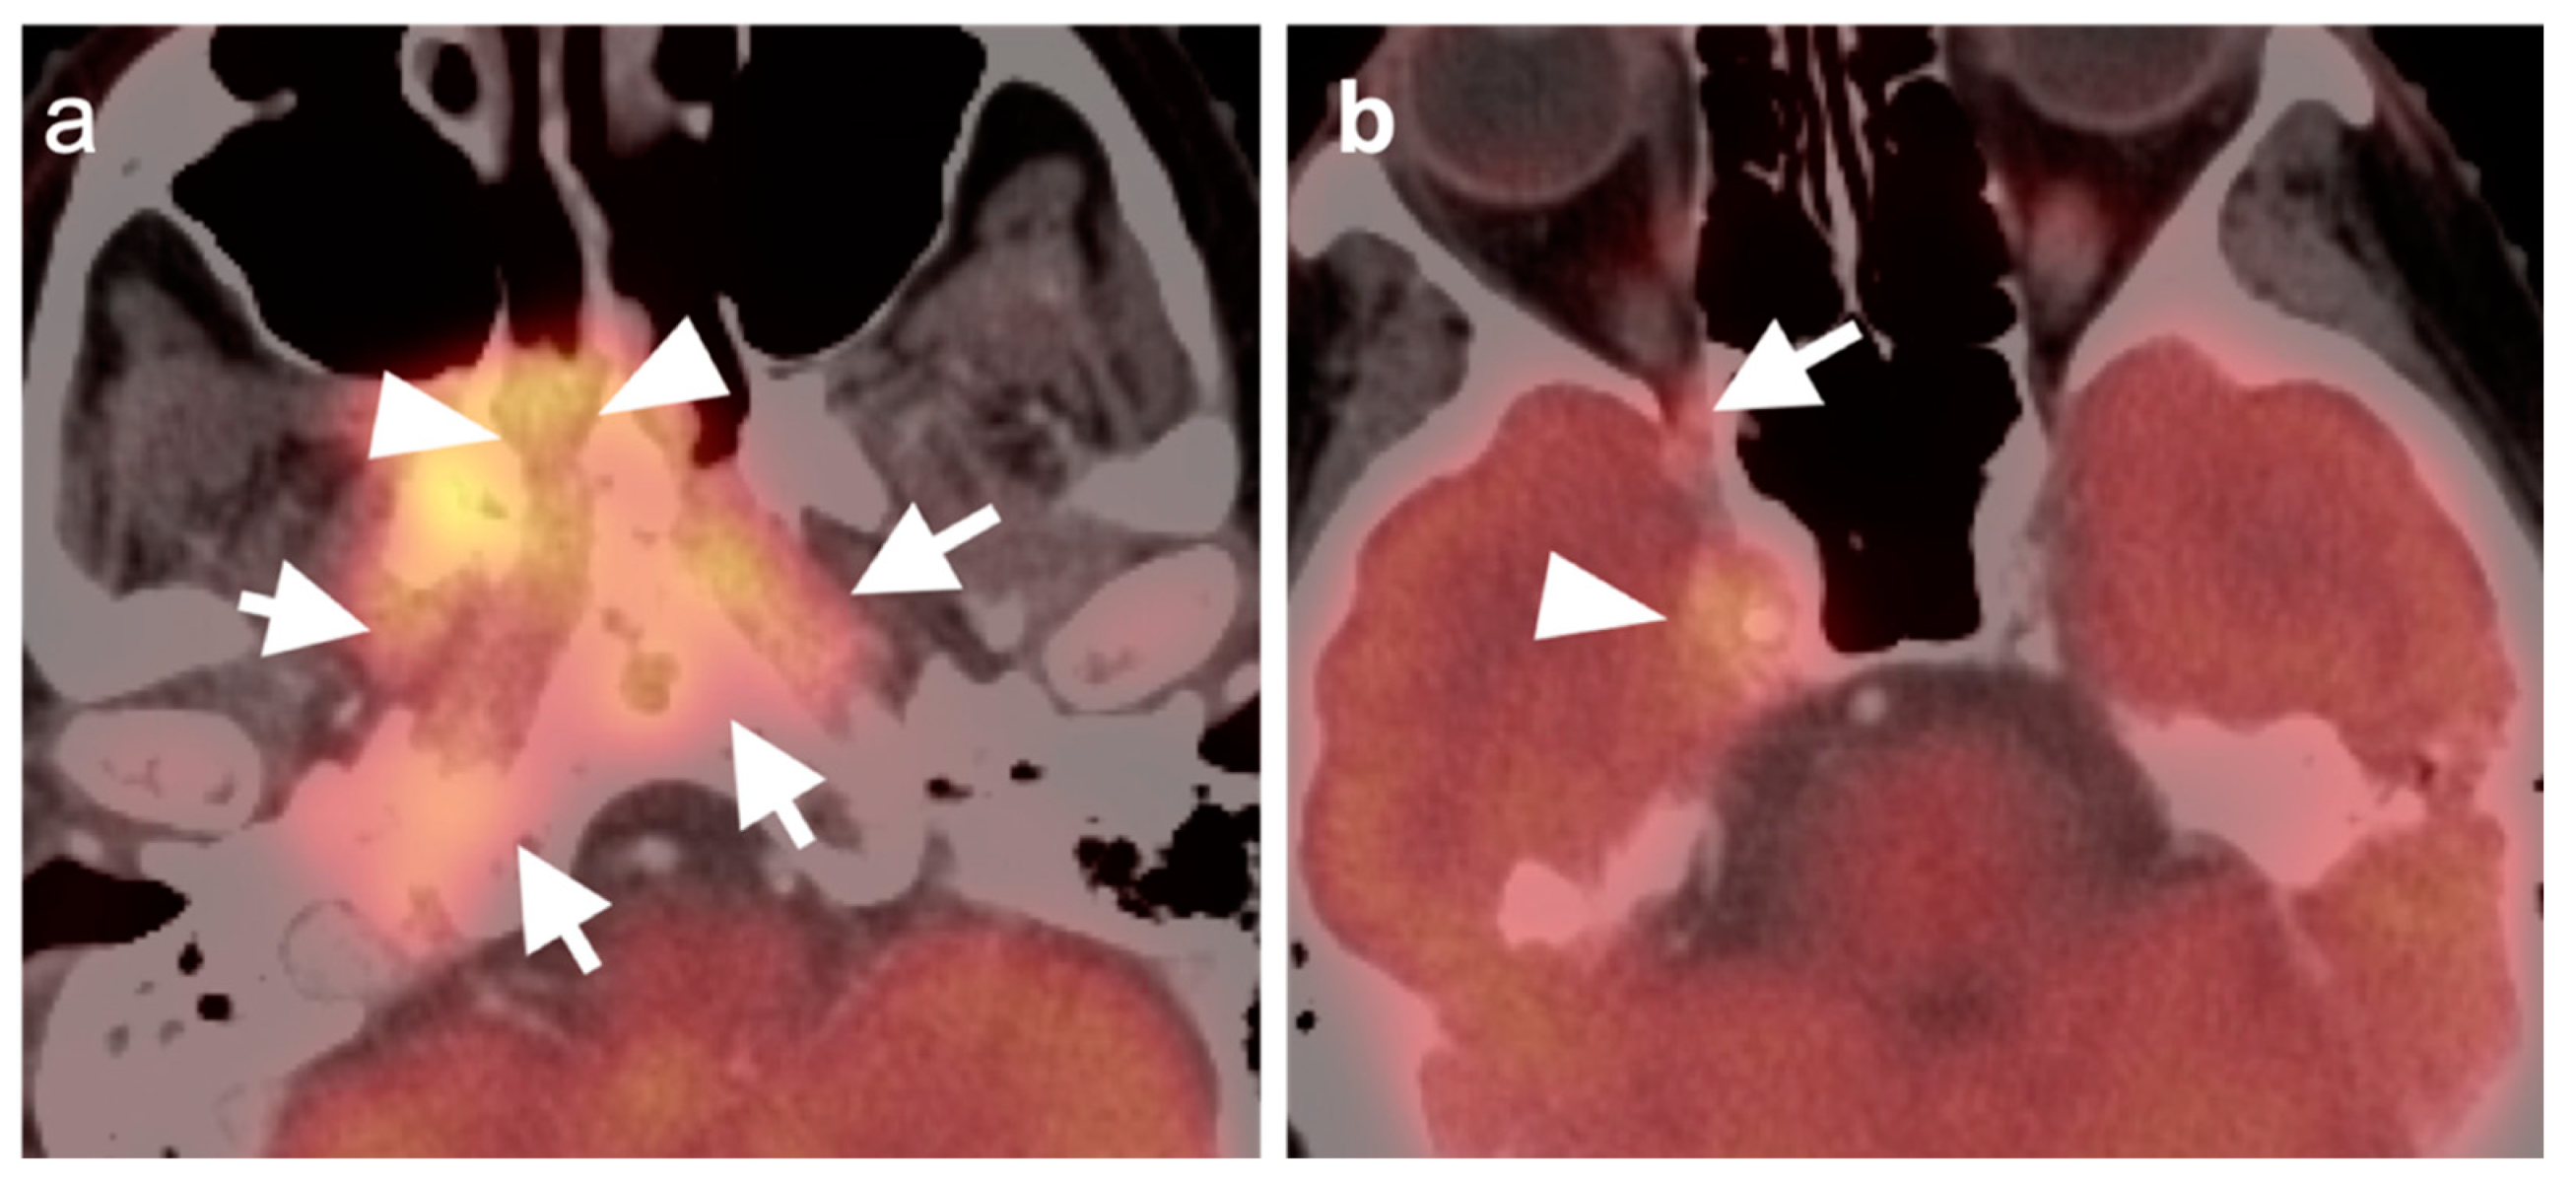

2.3. Nasopharyngeal Carcinoma

2.4. Sinonasal Tumors